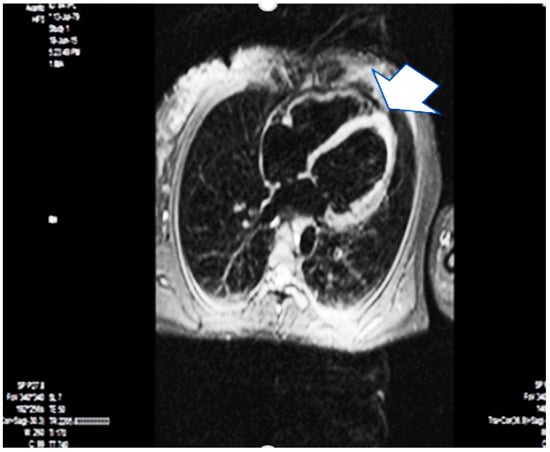

| first year | 1. no cardiac sighs 2. nuclear magnetic resonance imaging of the heart- EF- 50% 3. data on the previous apical myocardial infarction 4. Finally diagnosis peripartum myocardial infarction 5. Therapy with beta blocker, ACE inhibitor, aspirin |